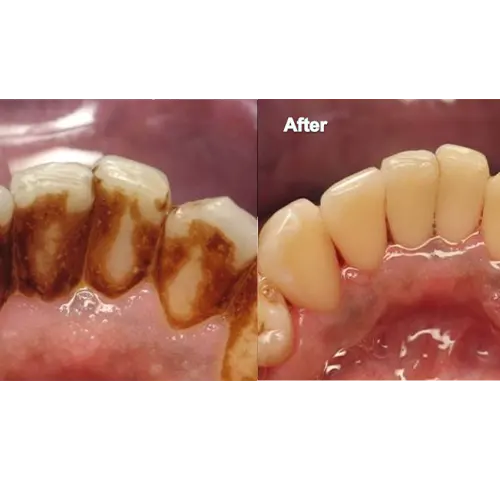

تغییر رنگ دندان‌ها و کدر شدن لبخند

جرم‌ها به دلیل جذب رنگدانه‌ها از غذاها، نوشیدنی‌ها (مانند قهوه، چای، نوشابه) و دود سیگار، باعث تغییر رنگ و کدر شدن دندان‌ها می‌شوند. این امر زیبایی لبخند شما را تحت تاثیر قرار داده و باعث کاهش اعتماد به نفس می‌شود. جرم‌گیری، لایه‌های سطحی جرم و لکه‌ها را پاک کرده و لبخندی روشن‌تر و سالم‌تر را به شما باز می‌گرداند.

۴. پولیش دندان: سطحی صاف و درخشان